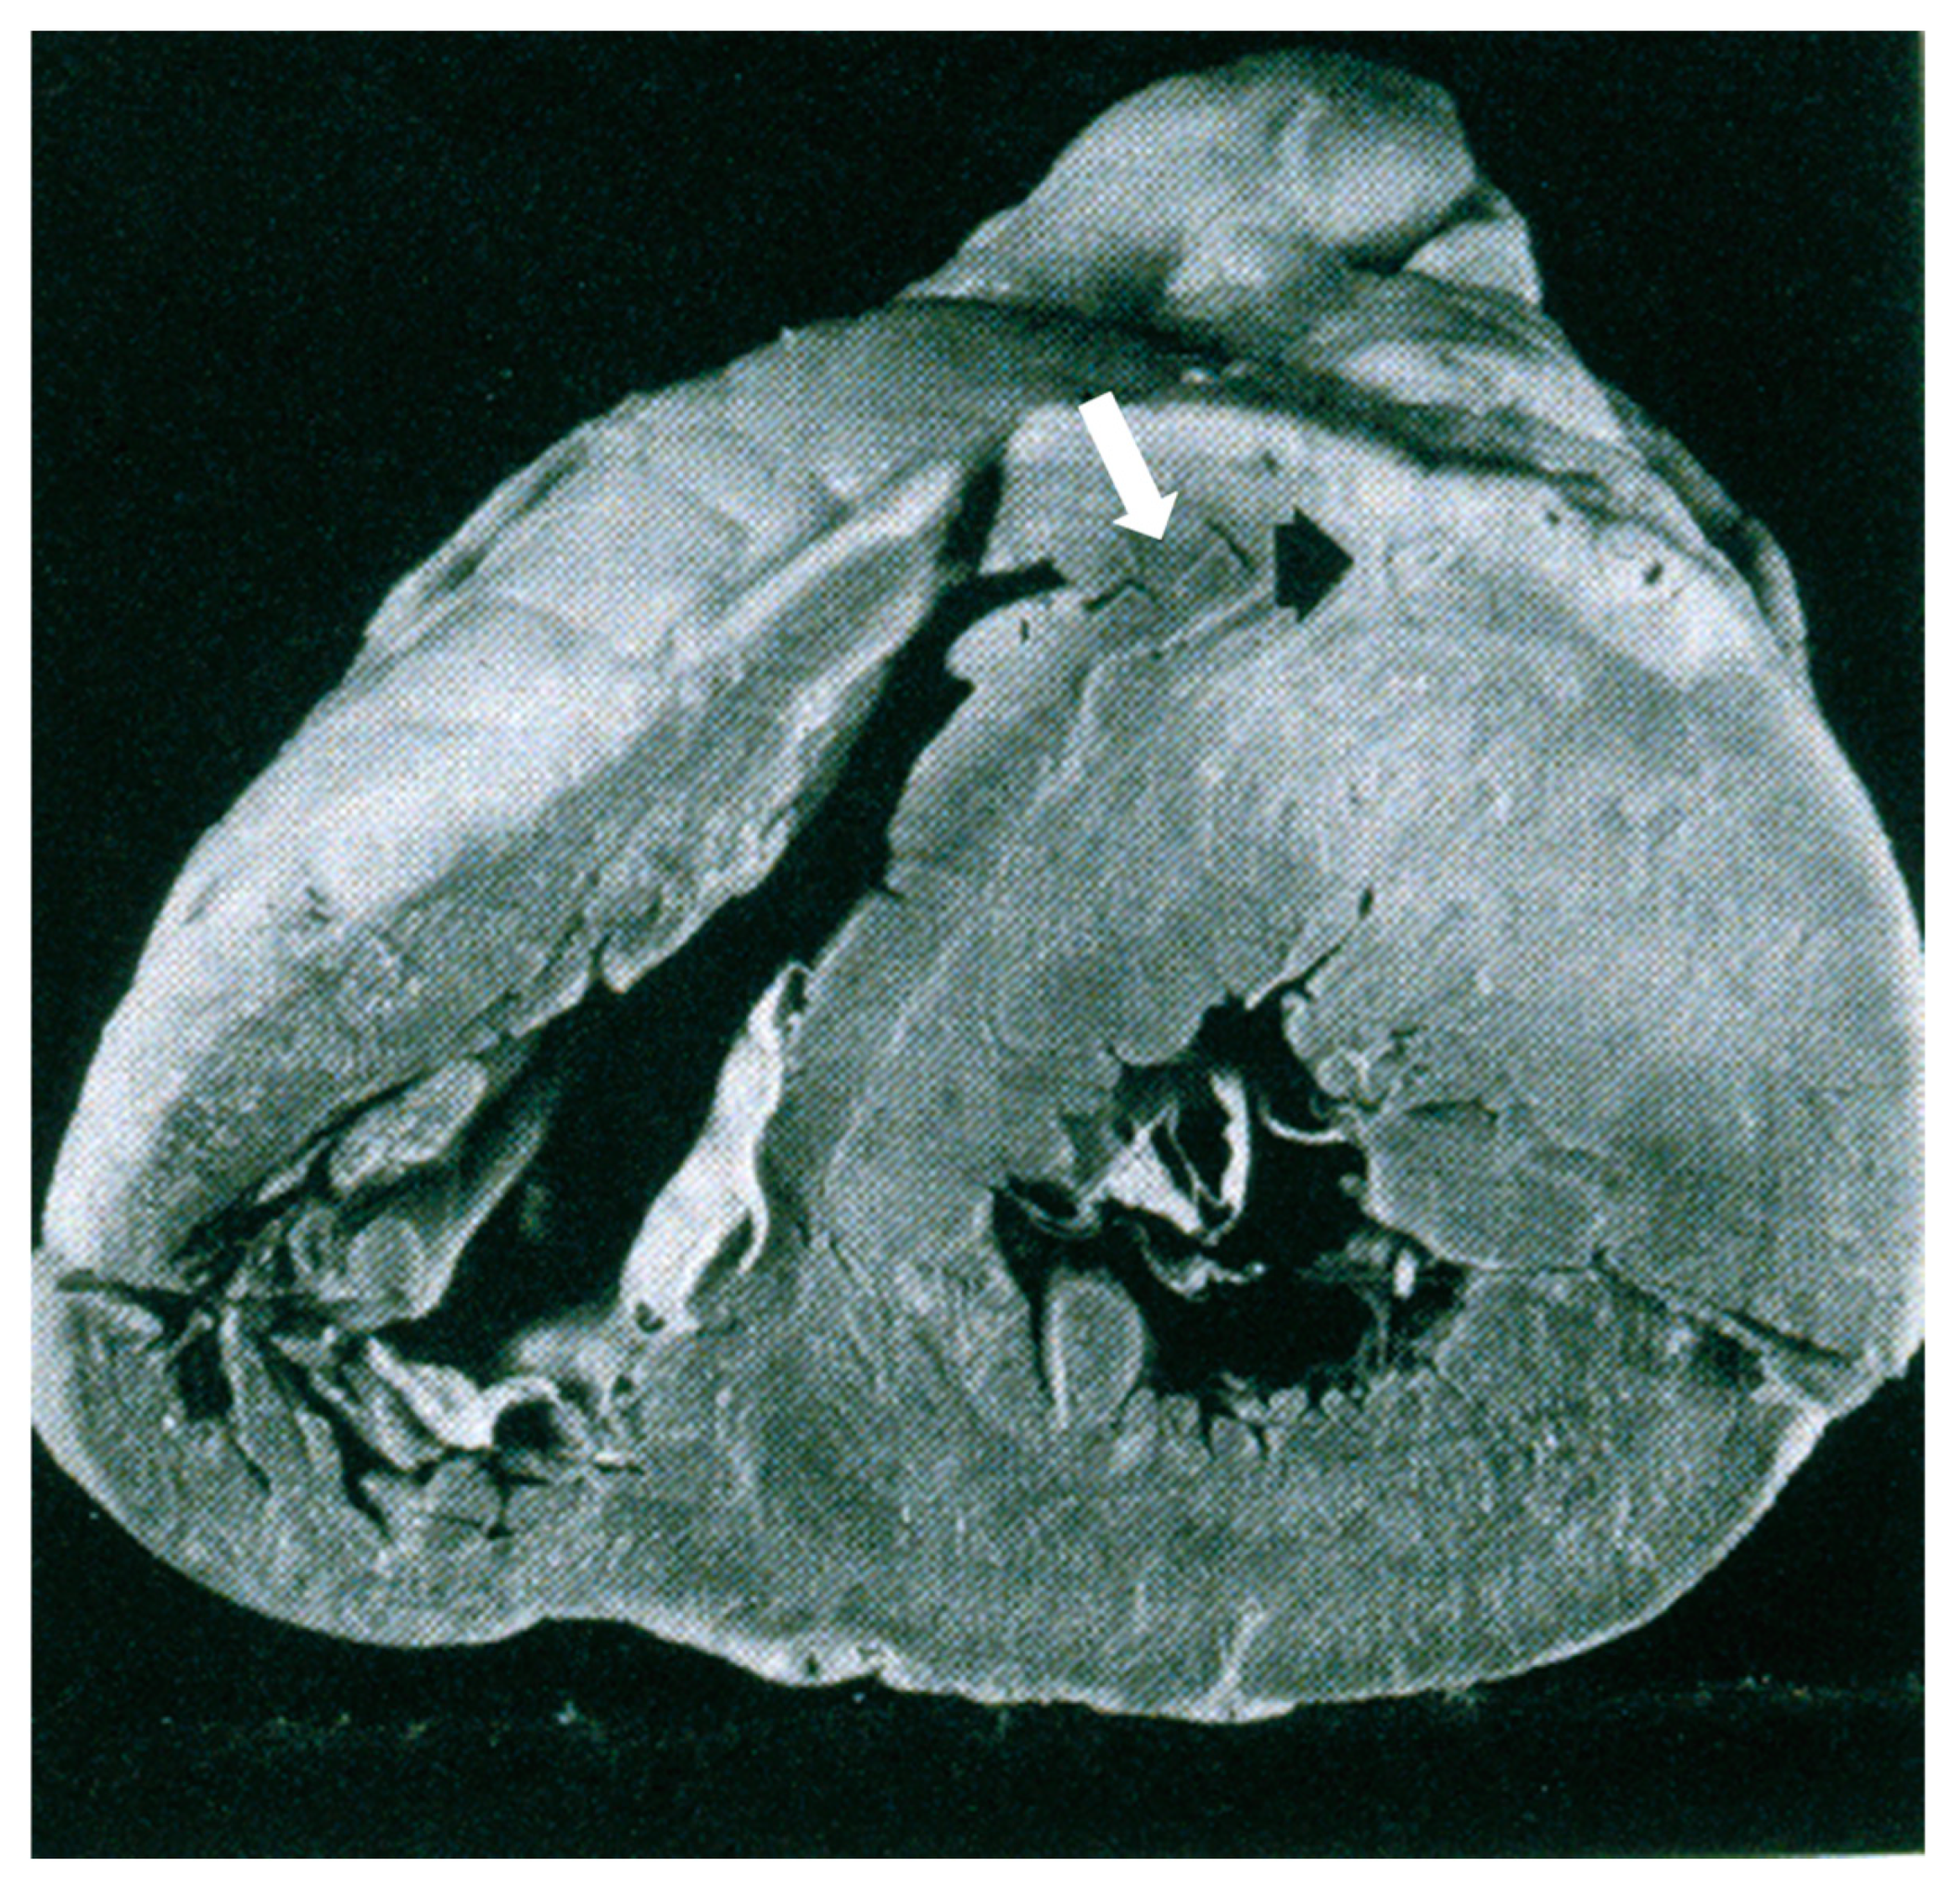

1. The Pathology Spectrum of Hypertrophic Cardiomyopathy

- Angelini, A.; Calzolari, V.; Thiene, G.; Boffa, G.M.; Valente, M.; Daliento, L.; Basso, C.; Calabrese, F.; Razzolini, R.; Livi, U.; et al. Morphologic spectrum of primary restrictive cardiomyopathy. Am. J. Cardiol. 1997, 80, 1046–1050. [Google Scholar] [CrossRef]